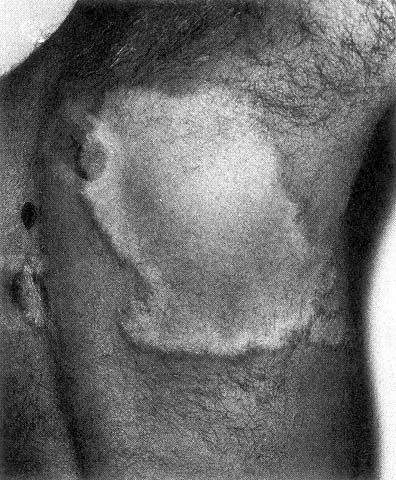

LEPRA TUBERCULOIDE

Lepra tubercoloide

Lepra tubercoloide (TT) - poche lesioni cutanee.